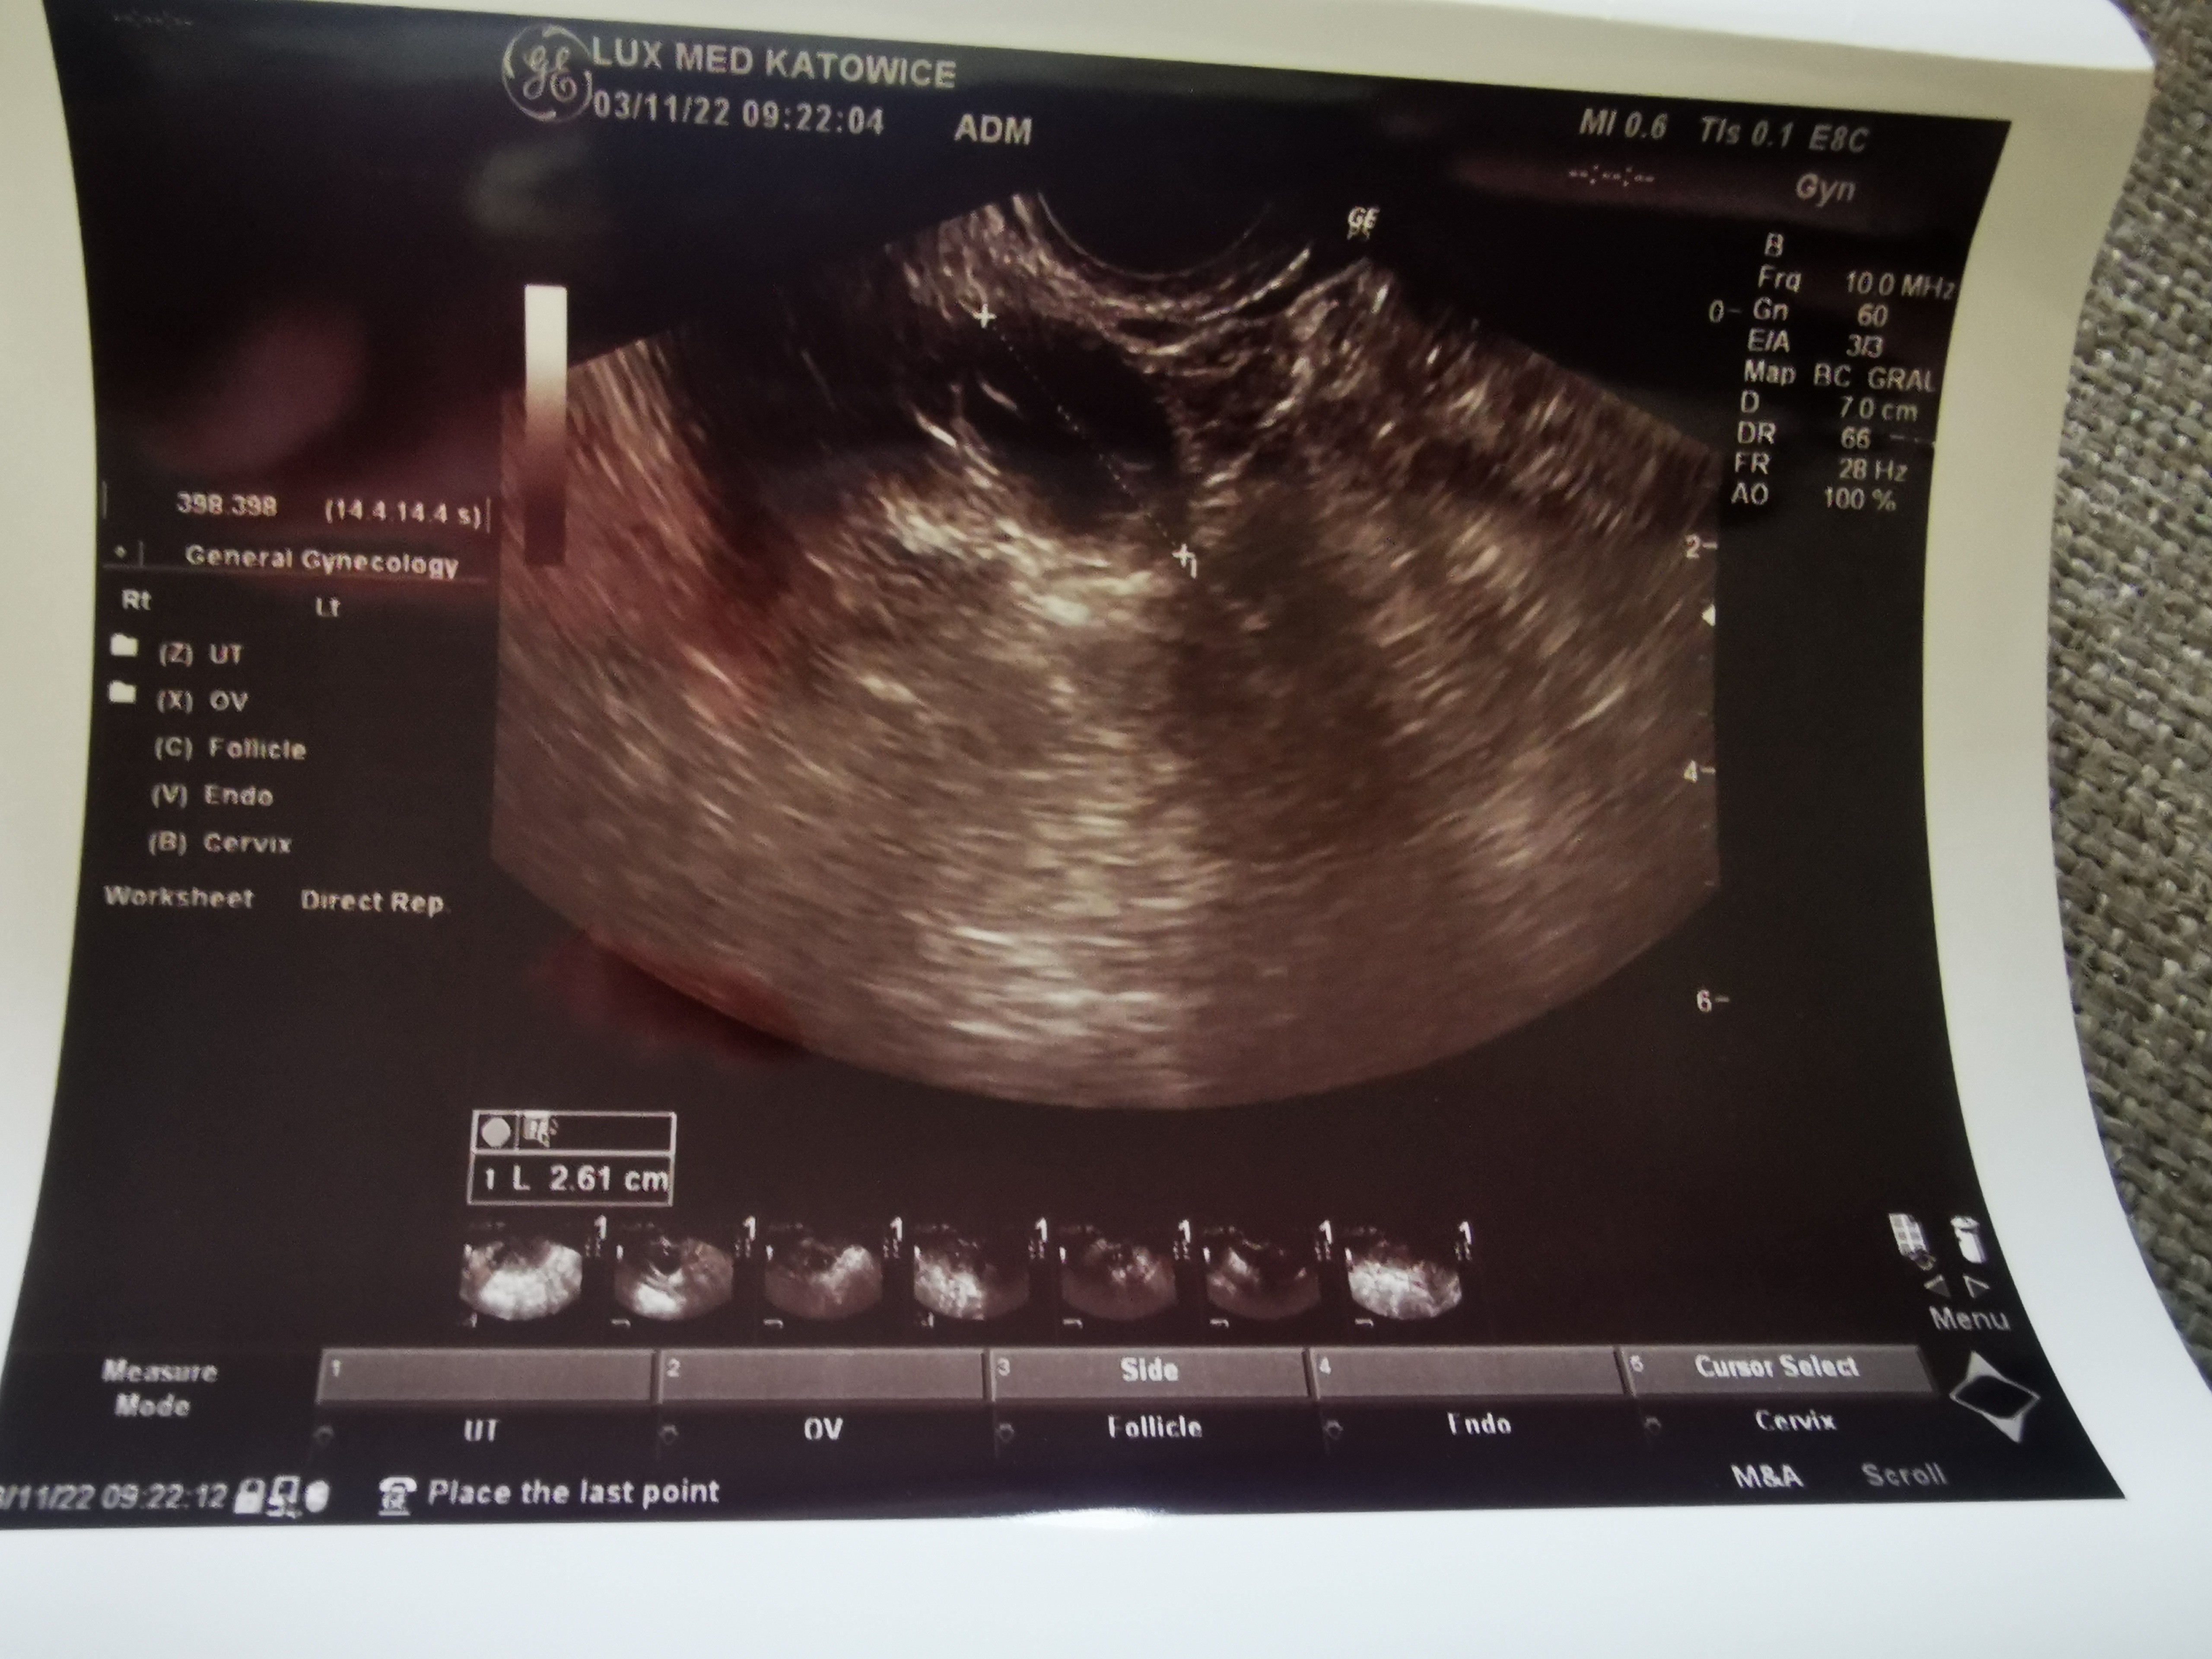

Zrobię jutro proga, bo jak badałam 3 listopada to był <0.1 i żadnych dominujących pęcherzyków.

Mam to trzymać do następnej wizyty 😂 to z 3 listopada. W ogóle nic nie kumam 😂🤷‍♀️, ale dla porównanie przy następnym monitoringu🤷‍♀️